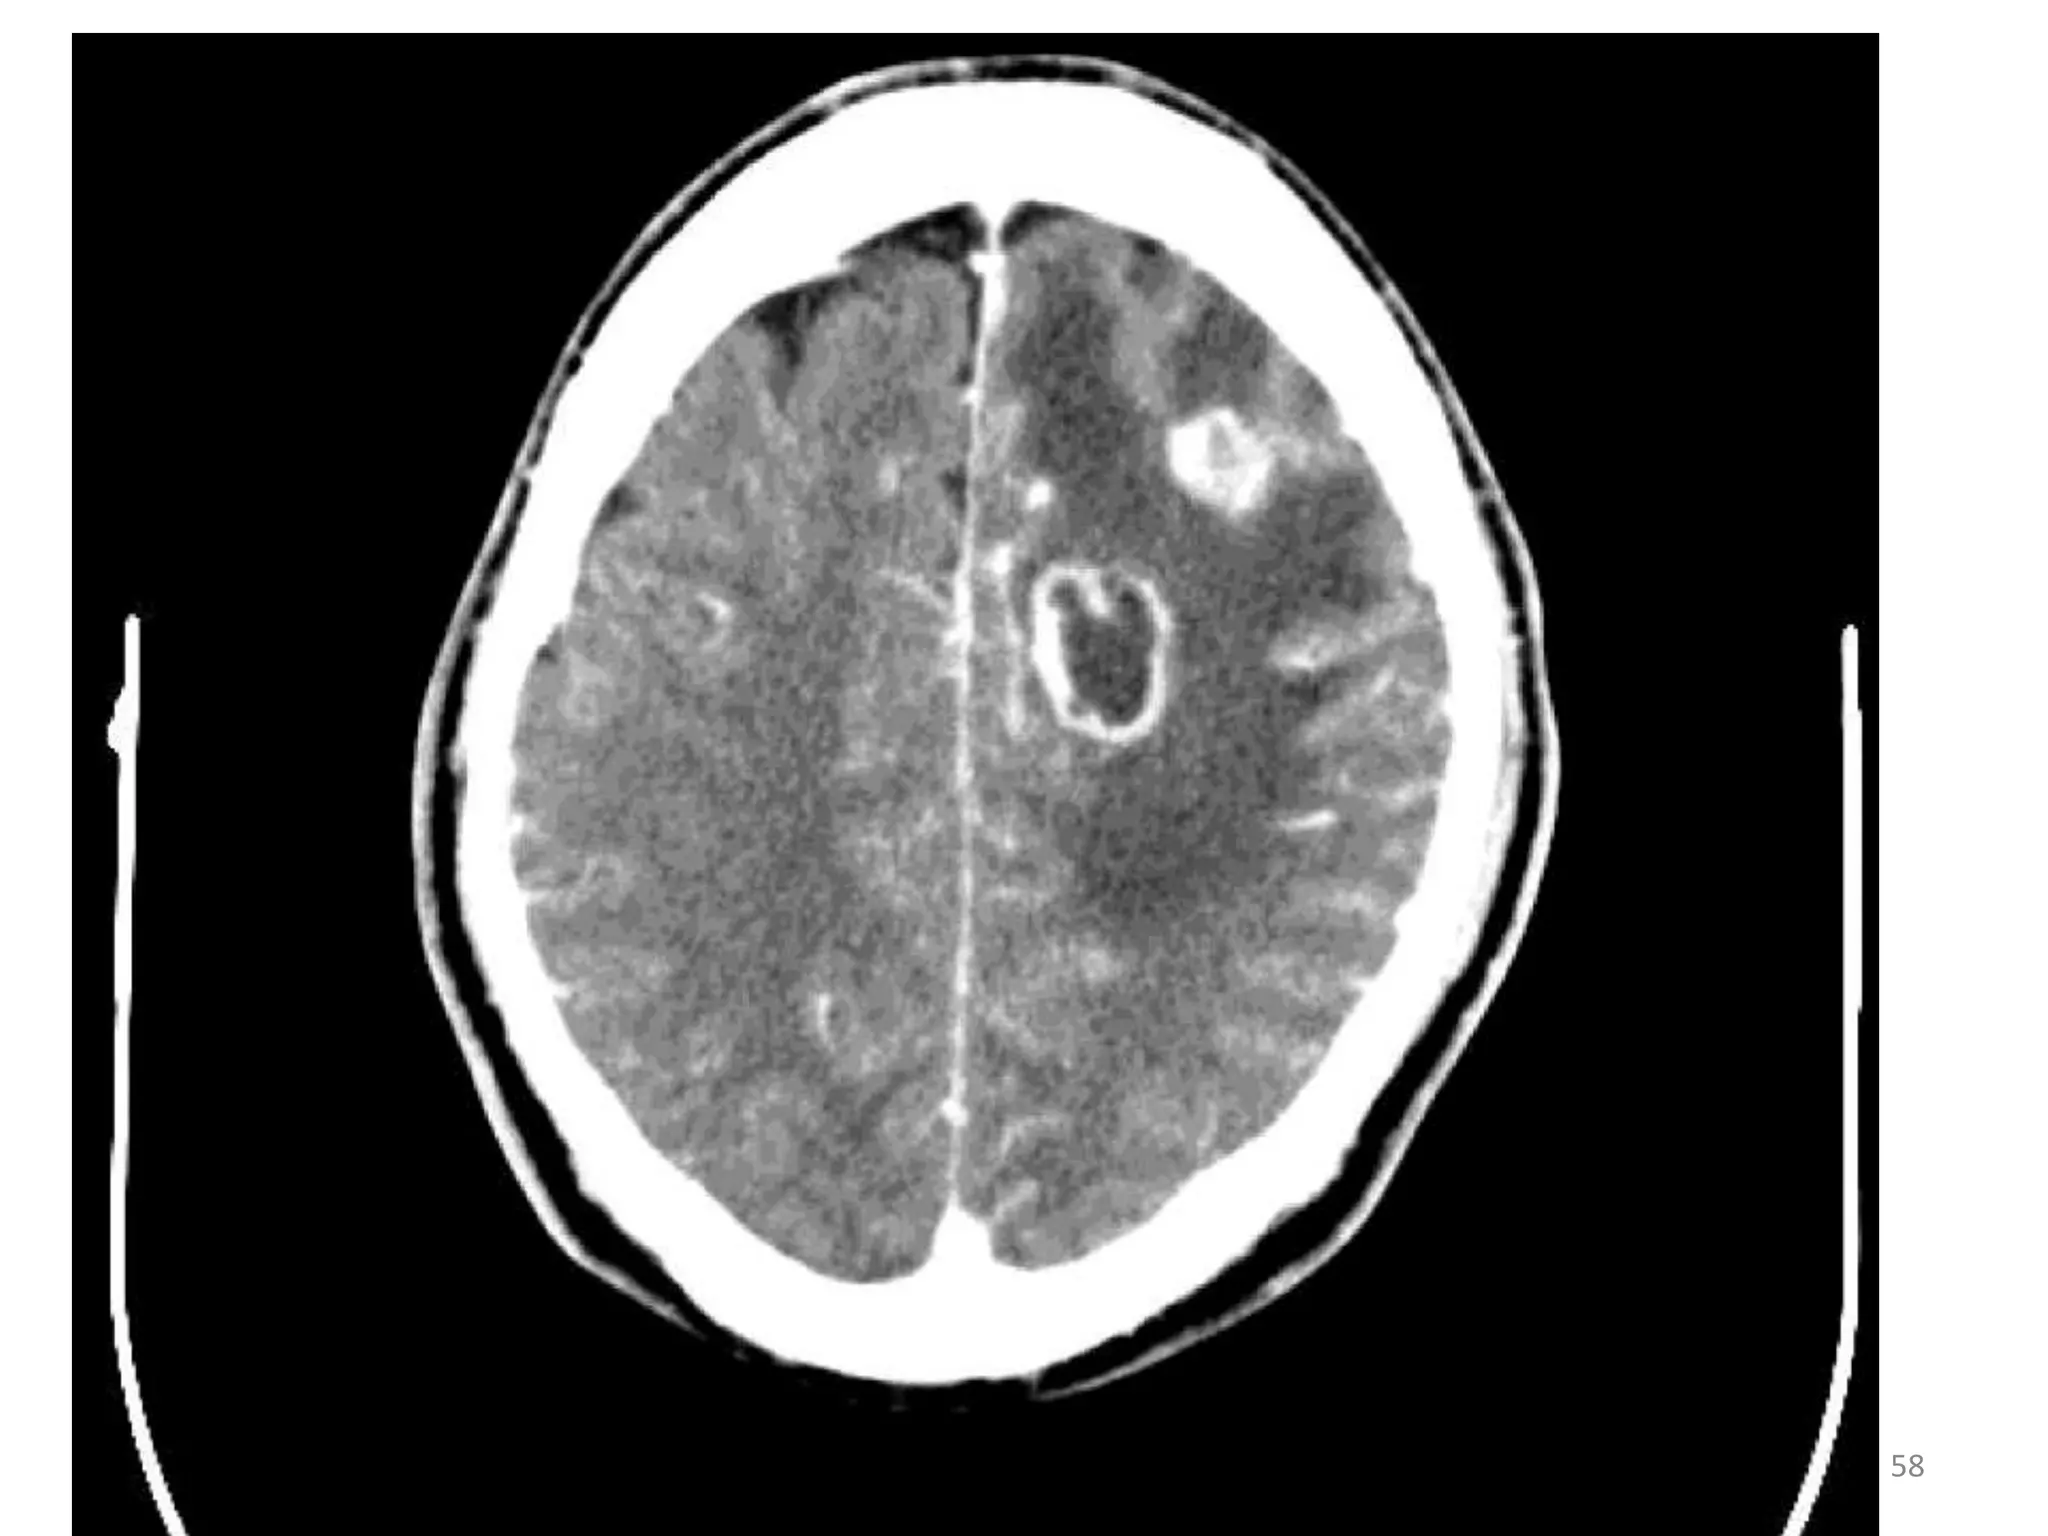

TOXOPLASMA GONDII:

• Results in mild subclinical illness in

immunocompromised with formation of latent

tissue cysts which persist for life.

• Acquired from ingestion of food contaminated by

cat feces or undercooked meat.

• Manifests when CD4+ cell count is below 100/μL.

• Presents with headache, fever, drowsiness, fits,

and focal neurological signs, retinitis may coexist.

• MRI shows multiple ring enhanced lesions in

cortical grey white matter.

57

58

• #59 T1 weighted MRI scan demonstrates peripheral enhancing lesion in the right frontal lobe with an eccentric nodular area of enhancement. ACCENTRIC TARGET SIGN